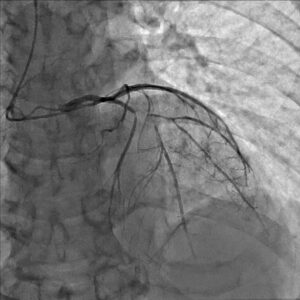

安静時狭心症の診断には、労作性狭心症にもまして詳細な症状の聴取が重要です。専門医が症状を詳細に聴取することで、ほぼ100%の診断が可能と言われています。疑わしい場合は、発作時にニトロペンの舌下使用を試し、著効するか否かで診断することもできます。カテーテルを使った冠動脈造影時に、アセチルコリンという薬剤を用いた冠動脈攣縮誘発試験で冠攣縮の有無を判定することが一般的です。

冠動脈の狭窄が急激に進行するために生じると考えられています。その原因は冠動脈の壁の中にできたコレステロールの塊(粥腫)が破れ、その部に血栓(血液の塊)が生じるためです。冠動脈造影検査をすると、多くの場合、血栓により冠動脈腔がほぼ閉塞状態であることが確認されます。